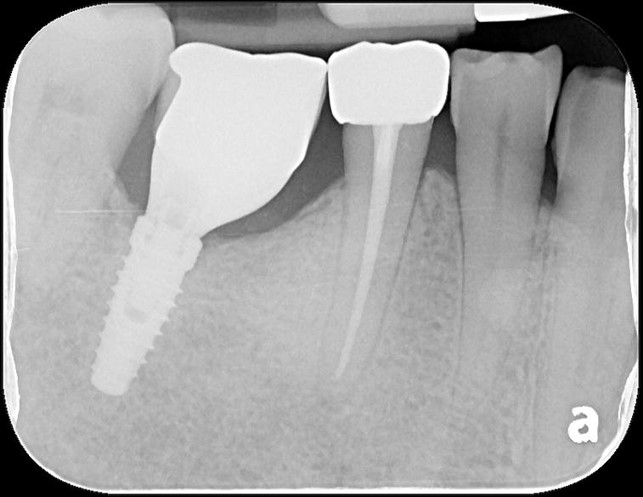

治療後根尖照

透過牙冠修復受損結構,患者逐漸適應